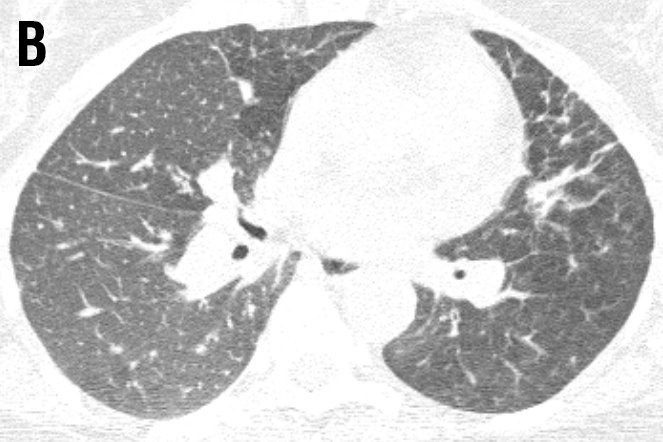

Figure 2 HRCT after six months treatment with adalimumab showing improvement; Oberstein score: LN 2; ND 1; LS 2; BVB 1; PC 1; PL 0; total score 7 [5,6].

Laboratory tests were normal except the soluble IL-2-receptor was increased (3981 kU/L). The lung function test were abnormal. Therefore, adalimumab was started, initially 80mg and than 40mg once a week subcutaneously. Methotrexate was also continued (7.5mg once a week). After six months her fatigue and arthralgia were less prominent and her quality of life (QOL) improved a lot. The FEV1 was enhanced from 42% to 58% of predicted, the FVC from 77% to 92% of predicted and the DLCO from 75 to 79% of predicted. The six-minute walking distance improved from 600 to 630 meters. More important, before the treatment she desaturated to 82%, and this did not happen anymore the last time she was tested. The HRCT also improved (figure 2 a and b) [5,6].